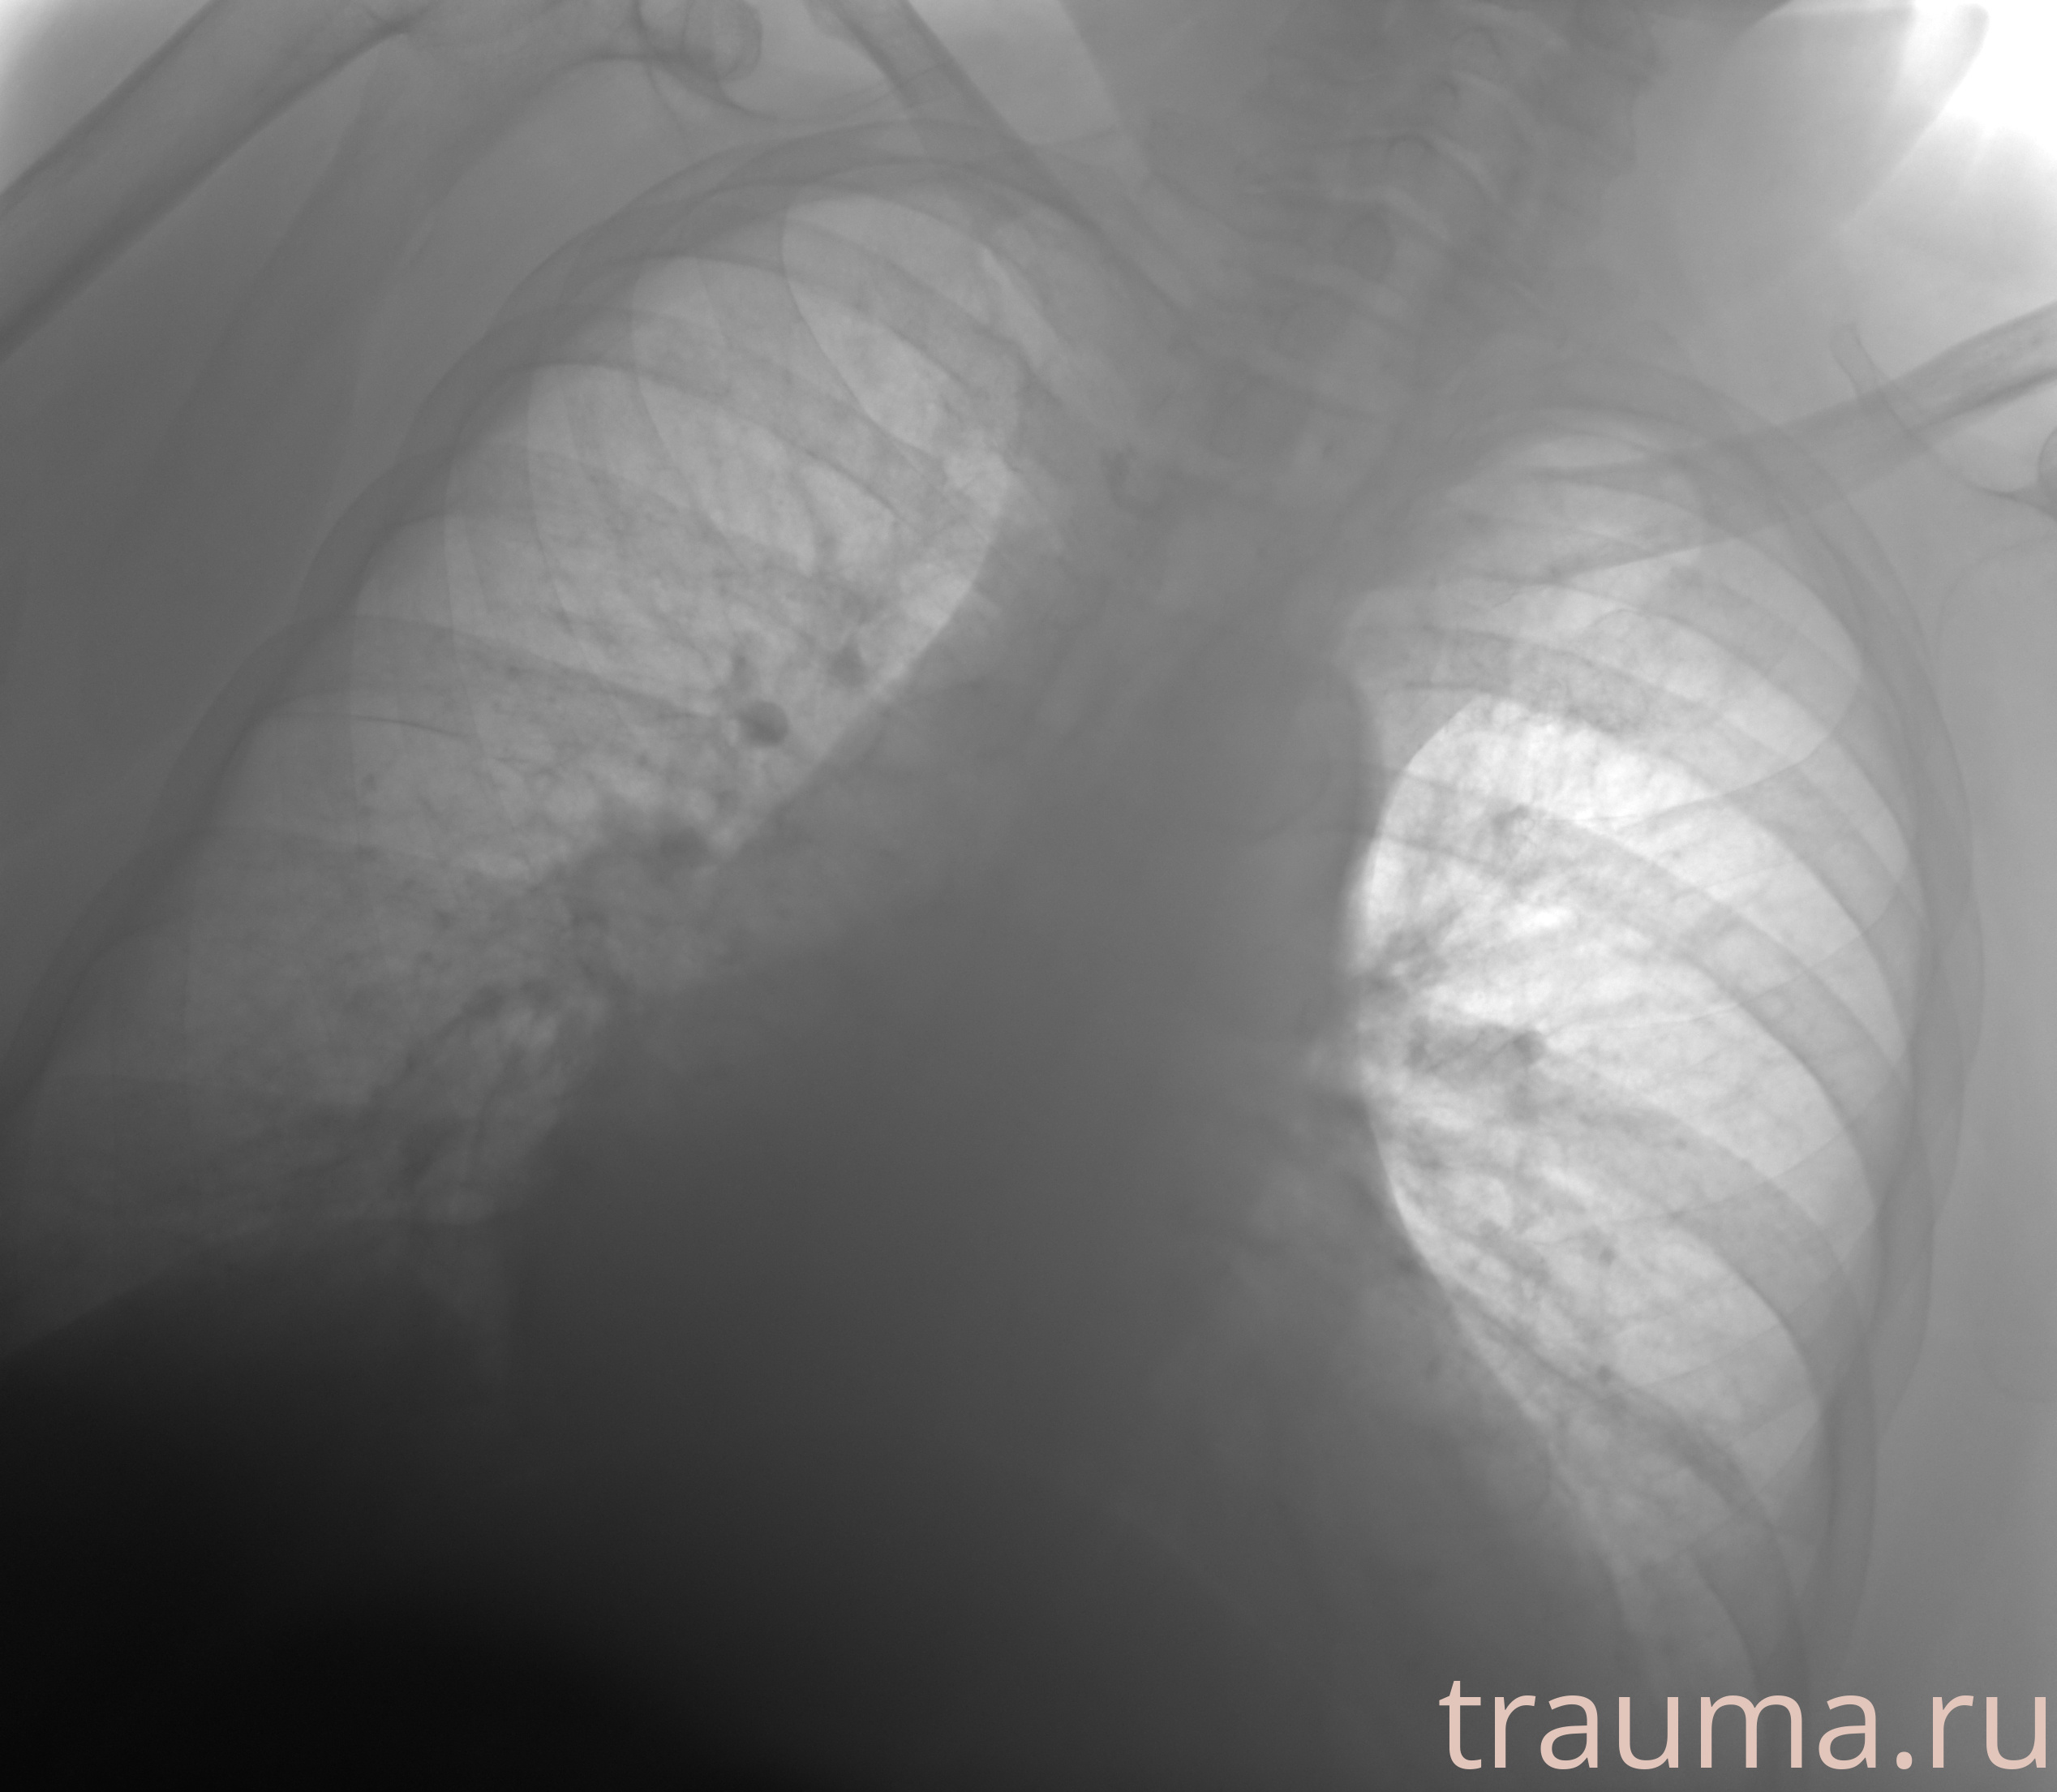

Рентген на дому: по вашему адресу приезжает врач-рентгенолог, травматолог-ортопед с мобильным рентгеновским аппаратом, проводит диагностику травмы или заболевания, делает необходимые рентгенограммы, дает рекомендации по дальнейшему лечению. Получить качественные снимки в домашних условиях возможно благодаря уникальной методике, разработанной МосРентген Центром для института  Склифосовского

при переломе шейки бедра и пневмонии от компании МосРентген Центр - партнера Института имени Склифосовского